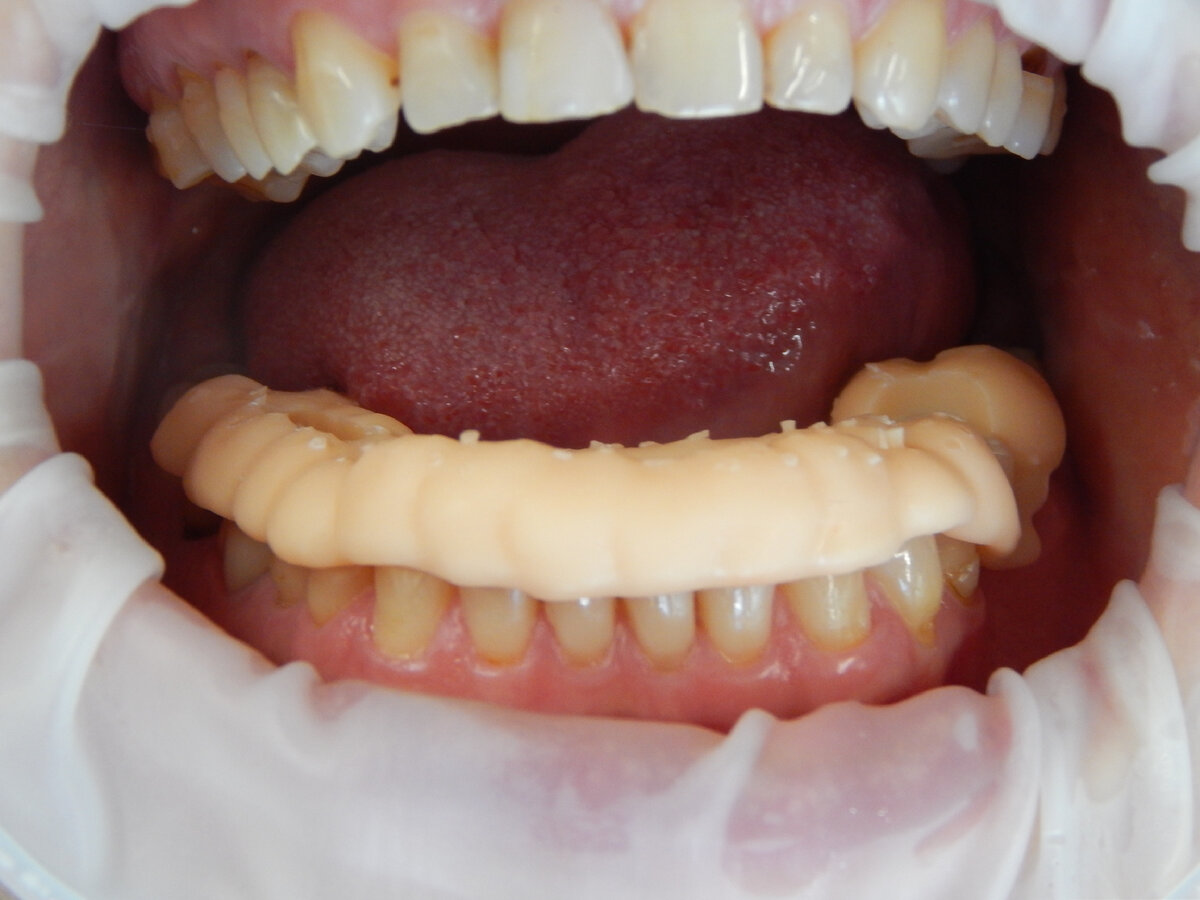

Ситуация до:

6 зуб слева снизу удален более 4 месяцев назад

Пациенту проведено сканирование, моделирование индивидуального шаблона в программе implant studio и его печать:

Шаблон фиксирован на зубах